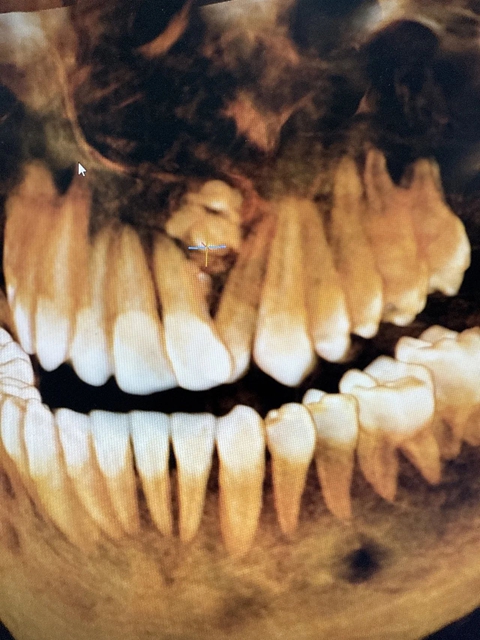

近日,一名13岁男孩在家属陪同下,到合江县中医医院口腔科要求矫正牙齿,男孩左上颌前牙严重错位,科室医生完善CBCT检查后发现,导致他牙列不齐的罪魁祸首竟然是——牙瘤!

CBCT检查

CBCT(锥形束CT):精确定位瘤体大小、位置及与邻牙、神经关系。组合性呈多个小牙,混合性呈钙化团块。